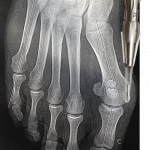

Hallux valgus

L’hallux valgus est une déformation de l’avant-pied qui concerne le gros orteil qui est dévié vers l’extérieur, entraînant une saillie au bord interne du pied appelée communément « oignon ».